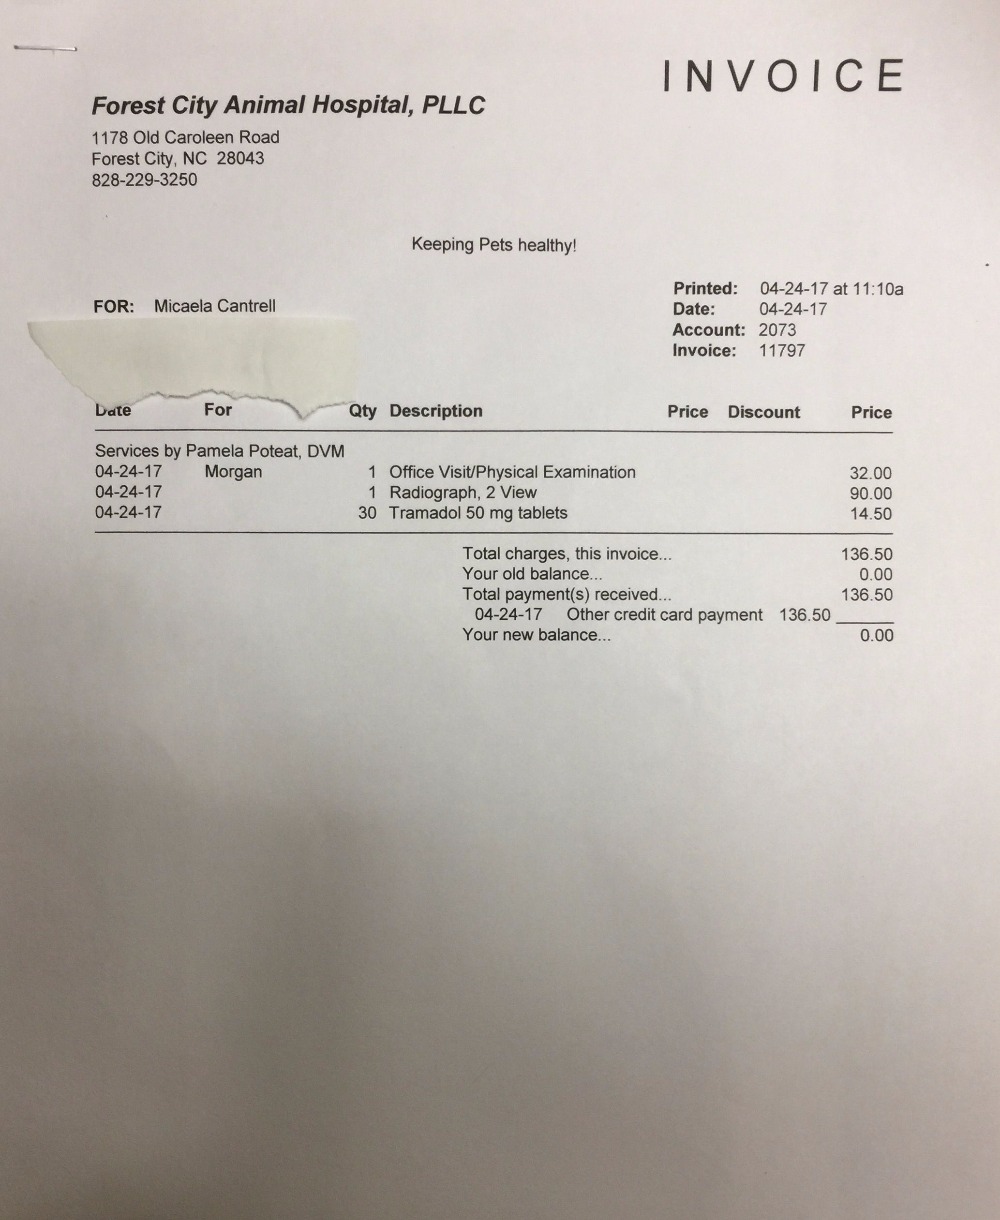

First, I want to thank everyone for their interest in helping this sweet girl. "Morgan" as she has been dubbed, was found on the side of the road (HWY 64 going into Morganton, NC) on 4/23/2016. It was super rainy and cold, and I was headed to Morganton to the feed store. We (my fiance and I) passed a dog sitting only 2-3 ft from the road in the pouring rain. I knew no dog would be sitting on the side of a super busy hwy in the wet and cold for no reason. We turned around and I jumped out of the car as quickly as possible, because we couldn't fully pull out of the road due to a ditch. I approached the dog and immediately realized my worse fears, that she had been hit. Without hesitation I immediately scooped her up, and this is where the story leads us. First off "Morgan" is extremely thin. No microchip, only a lime green collar with no tags. Looks to be (and comfirmed by vet) full-blooded Border Collie. Today she had X-rays and it was confirmed she has a fractured femur just above the knee on the right side, and another break to the bone that connects to the spine on the left side, and a fractured pelvis. She will require surgery and will be referred from the initial attending vet to someone for qualified to perform the surgery, because of the positioning of the femur break. She will require a plate in the femur. We are currently waiting on info from the Orthopedic Specialist of the initial vets choosing, and I will update as I get more info. Intitial vet believes surgery costs o be anywhere from $1200-$1800 (could be more). I WILL NOT give up on this girl, even if her owners have. If you are unable to help financially, prayers and good wishes are just as important and just as appreciated. Initial attending Vet is Dr. Pam Poteat at Forest City Animal Hospital in Forest City, NC. If you would like to confirm they do have a Facebook page with their phone number listed, but I will not list it here out of respect for them. The Orthopedic Surgery will be performed as soon as we can get a refferal and an appt. The Community Pet Center (a 501c3) organization will also be accepting donations on behalf of Morgan for those that would feel more comfortable donating to an organization rather than an individual. I would also like to speak on behalf of Morgan, she has been nothing but an angel and extremely trusting of me from the very beginning of our journey together, and she deserves to live out a long, healthy happy life. She is still very young and has so much left to see and do. Thankyou so much from the bottom of my heart.